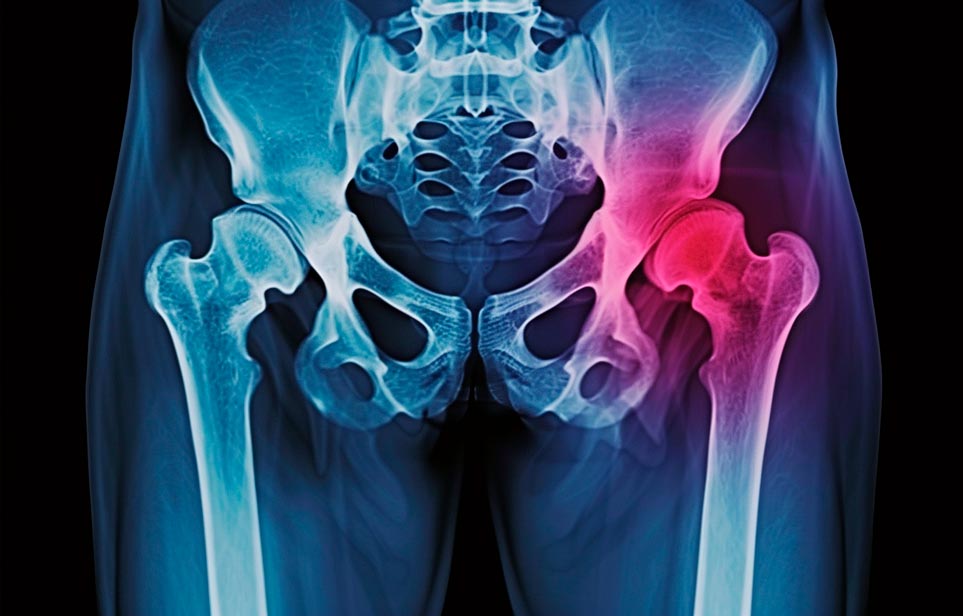

Такая травма в большей части случаев возникает у граждан преклонного возраста. При её появлении на протяжении длительного времени сохраняются болевые и неприятные ощущения в области паха, при которых серьёзно ухудшается качество жизни, возникает множество последствий для его жизни и здоровья.

По какой симптоматике можно определить перелом шейки бедра?

Выявить его можно по возникновению следующей тревожной симптоматики:

- Визуально повреждённая нога сокращается на несколько сантиметром из-за сокращения мышц.

- Стопа выворачивается наружу.

- В лежачем положении человек не может поднять ногу.

При такой симптоматике важно незамедлительно обращаться к специалистам для получения всей необходимой помощи, терапии и восстановления после перелома шейки бедра. Если не оказать помощи старику, то это приведёт к гноению, инвалидности, иным видам осложнений.